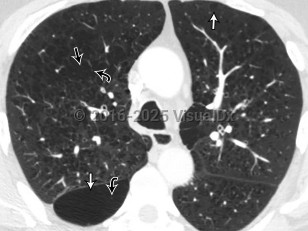

Imaging Studies image of Chronic obstructive pulmonary disease - imageId=8353431. Click to open in gallery.  caption: '<span>Axial non-contrast CT image of the chest viewed in lung windows in the upper lungs. CT image demonstrates several well-defined regions of low attenuation, both centrilobular (straight black arrow) and paraseptal (straight white arrows) distribution consistent with emphysema. Vessels course through several of these regions (curved black arrows), confirming that these areas reflect parenchymal loss rather than cysts (also note the lack of walls). There is severe airways thickening and mucous plugging, compatible with chronic bronchitis.</span>'

Axial non-contrast CT image of the chest viewed in lung windows in the upper lungs. CT image demonstrates several well-defined regions of low attenuation, both centrilobular (straight black arrow) and paraseptal (straight white arrows) distribution consistent with emphysema. Vessels course through several of these regions (curved black arrows), confirming that these areas reflect parenchymal loss rather than cysts (also note the lack of walls). There is severe airways thickening and mucous plugging, compatible with chronic bronchitis.